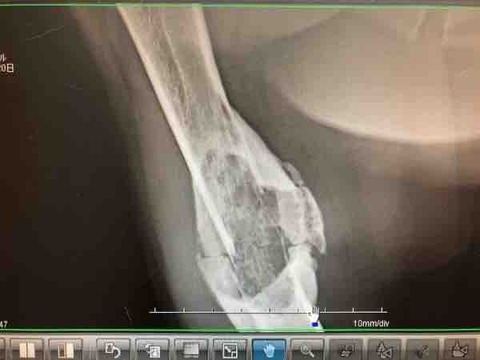

IMG_1073

骨折治療中だった脚が急にボコボコしてきたのが、6月(この写真は6/14)

この脚が…たったの2ヶ月で↓

IMG_1074

右前脚が骨折したのは6月21日

IMG_1066

たったの3ヶ月でこんなに大きくなってしまいました

骨肉腫が大きくなるスピード、めちゃくちゃ早い